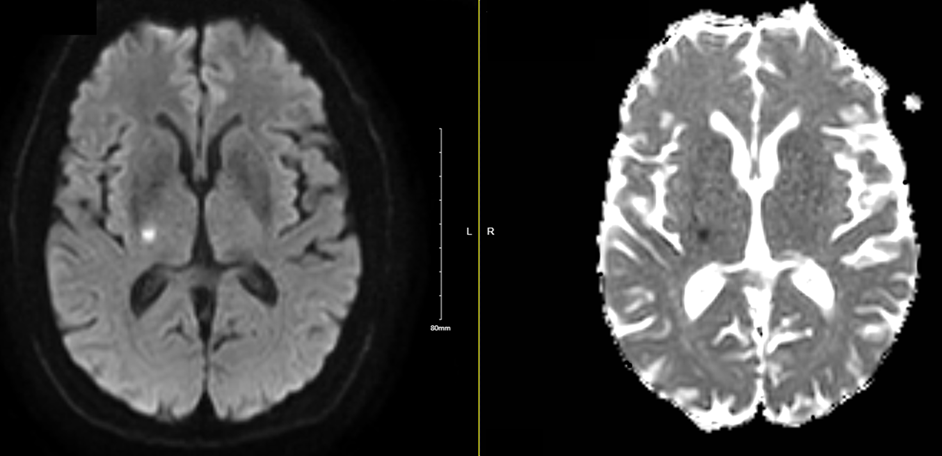

Results: The patient’s pre-stroke symptoms included severe bilateral upper extremity postural/kinetic tremor as illustrated in Figure 1 [figure1]. Post-stroke symptoms included mild left hemiparesis and sensory loss, postural/kinetic tremor in right upper extremity only. MRI shows abnormal restricted diffusion in the right internal capsule and thalamus (Figure 2)[figure2], posterolateral to the expected location of the VIM based on MRI atlases.

MRI DWI and ADC sequences showing ischemic stroke